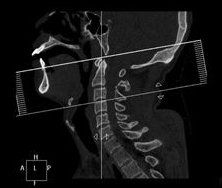

檢查方式

頸髓損傷X片臨床上通常可以通過X線顯示的頸椎骨折脫位的部位對頸髓損傷節段作出判斷,但有時頸椎的變化並不明顯,因此

需通過仔細檢查皮膚感覺障礙、肌肉運動障礙及反射的變化來確定。在解剖和功能的關係中,許多神經分布是交叉或重疊的,檢查時必須仔細加以辨認。有時甚至需經過反覆檢查,或從不同方向確定感覺障礙平面,才可獲得較準確的結論。頸3-4支配整個上頸部感覺,並表現為披肩狀分布的上胸部感覺。下位頸段損傷範圍需通過檢查上肢感覺分布來確定。